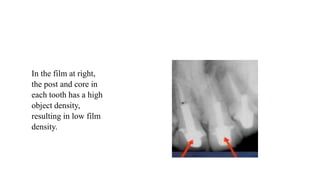

In the film at right,

the post and core in

each tooth has a high

object density,

resulting in low film

density.